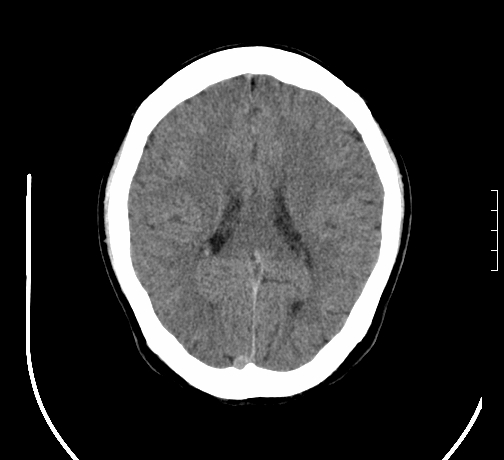

女,28岁,幼时有癫痫,常有发作,服药后可几月不发作,走路不稳3-4月,加重一月。

患者出现走路不稳是近几个月的事,而癫痫则有幼时就有,常发,则会常服药,癫痫药可引起小脑综合症,小脑萎缩,而小脑发育不良的主要症状不是癫痫

考虑癫痫,长期间断发服抗癫药,导致小脑综合症,小脑萎缩

不知现在还有没有癫痫,应该另有致痫灶,进一步检查。